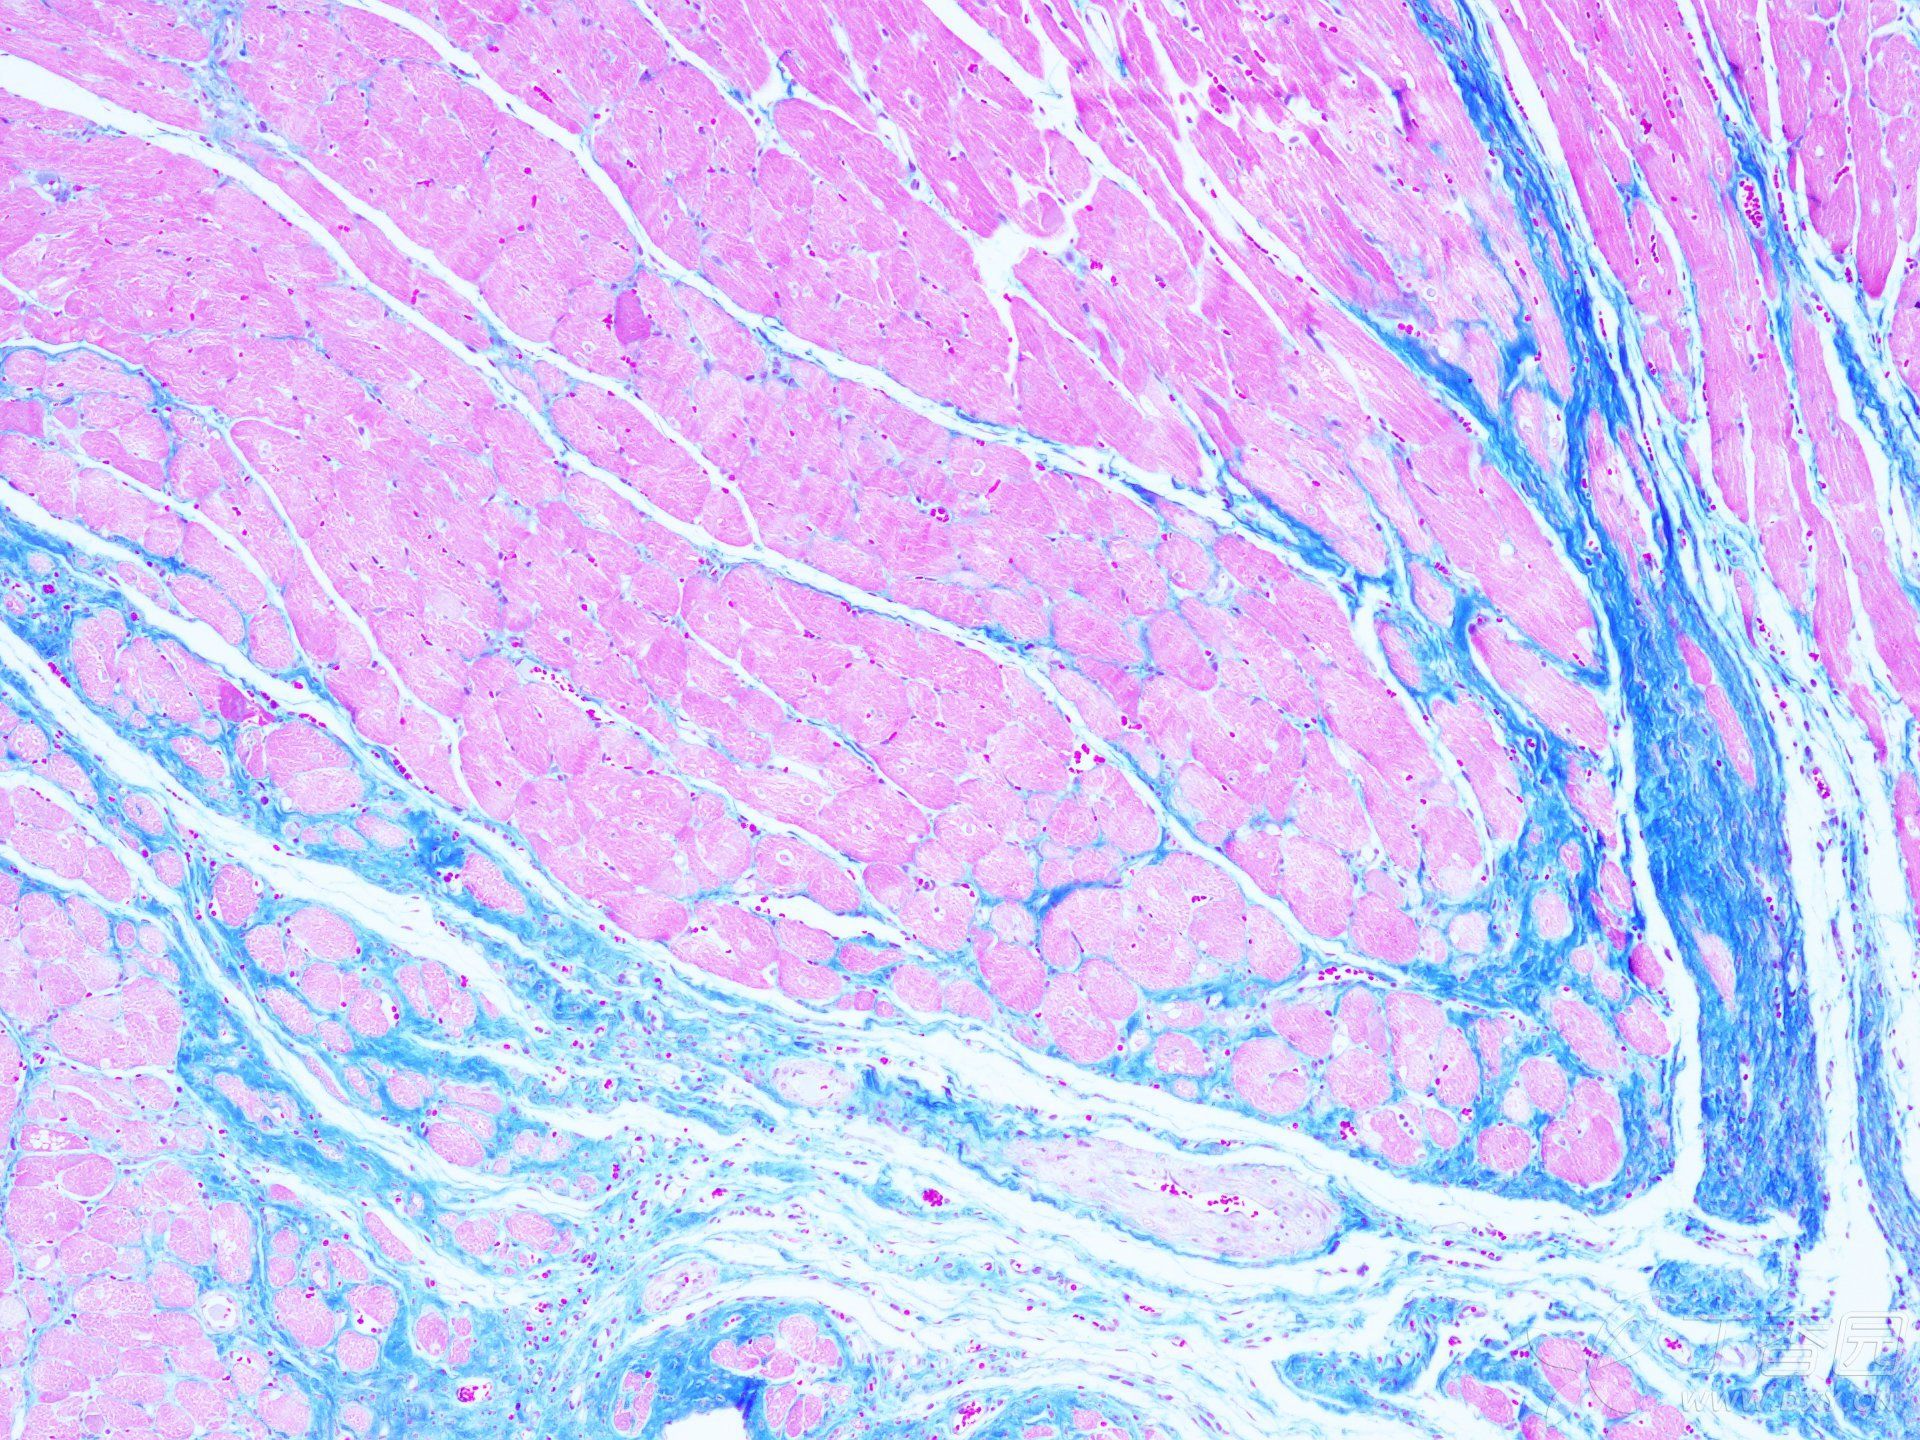

MASSON染色實驗技術注意事項由普拉特澤生物為大家總結分享,普拉特澤生物病理染色實驗平臺專業承接HE染色實驗外包、油紅O染色等組織染色實驗代做服務,積累專業豐富的實驗操作經驗。上次我們分享Masson染色實驗報告分析不夠詳細,有一些注意事項沒有寫出來,那今天咱們就為大家專門出一期詳細探討MASSON染色實驗技術注意事項,幫助大家更好的理解和應用這個技術,快點學起來吧!

MASSON染色作為一種重要的組織學染色方法,具有廣泛的應用價值。然而,要想獲得準確的染色結果,我們需要注意多方面的因素。從選擇合適的組織樣本、嚴格控制染色時間和溫度、注意染色劑的配制和保存,到細心觀察和處理染色結果,每一個環節都至關重要。

為了提高MASSON染色的準確性和可靠性,我們建議大家在實驗前充分了解相關知識和技巧,并嚴格按照實驗步驟進行操作。同時,我們還可以結合其他染色方法和技術,如免疫組化、熒光染色等,以更全面、深入地研究組織結構和功能。

總之,MASSON染色雖然具有一定的復雜性和挑戰性,但只要我們掌握了正確的技巧和方法,并嚴格遵循實驗步驟和注意事項,就一定能夠獲得準確、可靠的染色結果,為生物學和醫學研究提供有力的支持。